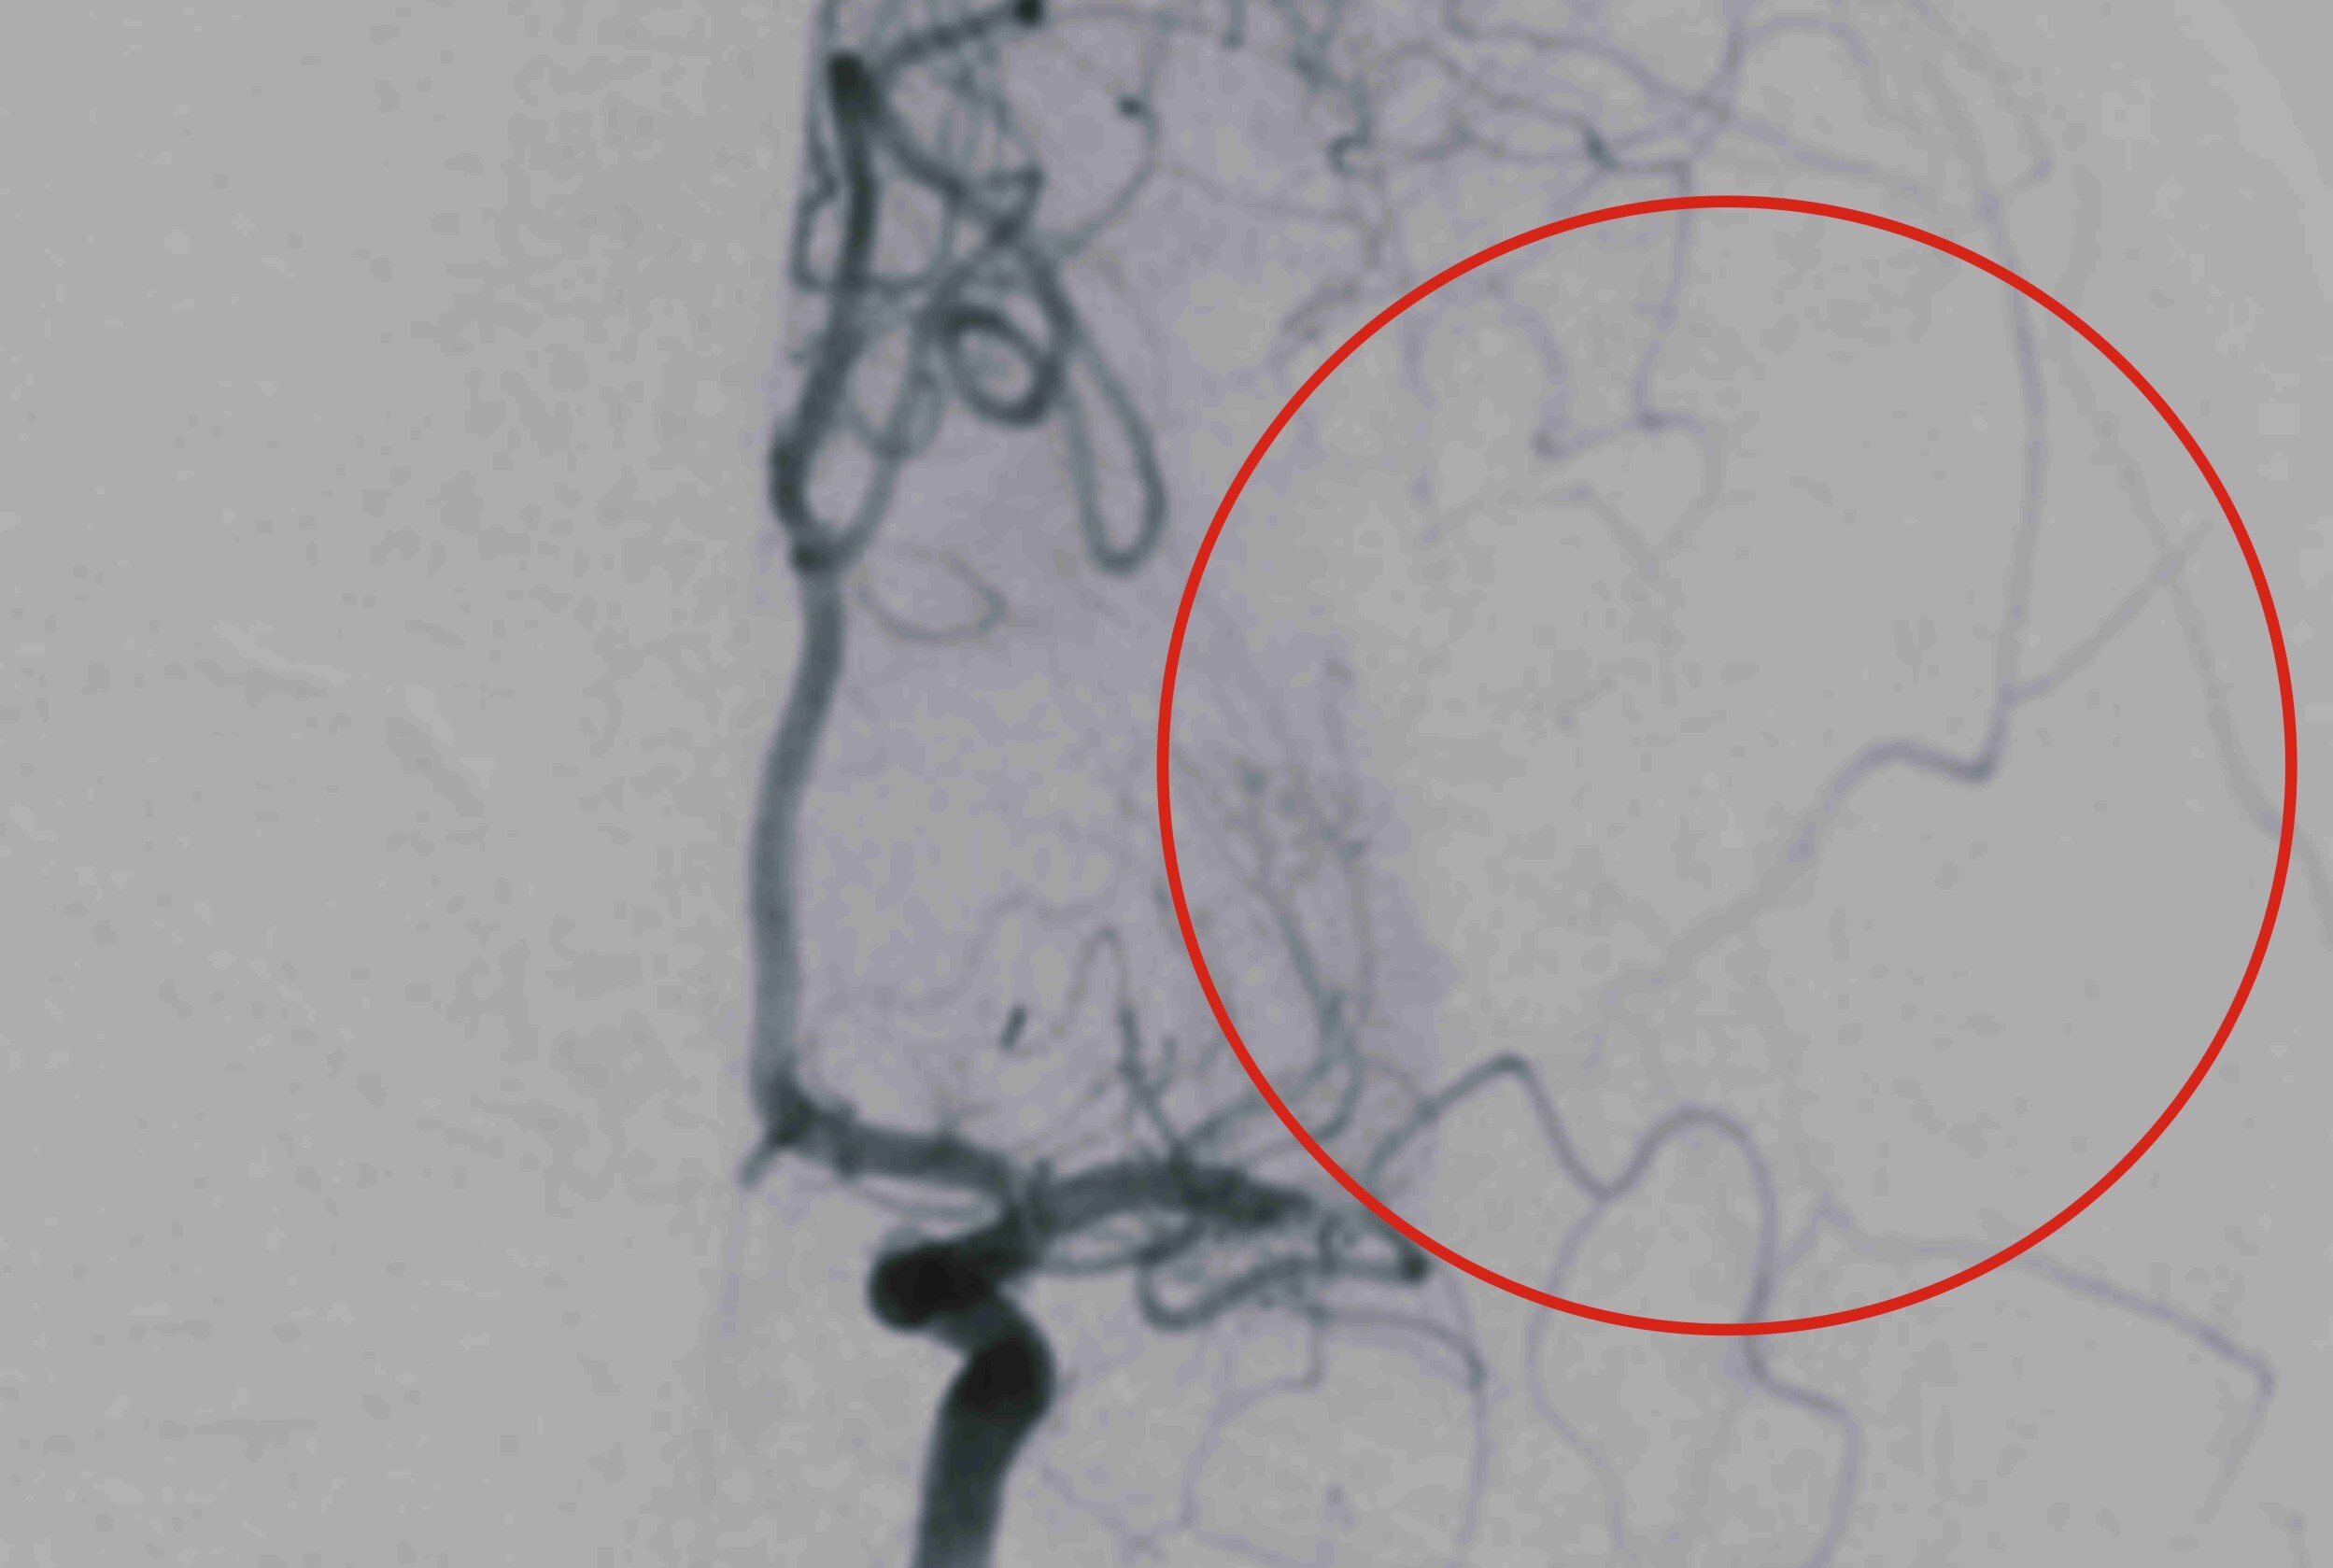

▲ 小惠(化名)接受取栓治療前,左側中大腦動脈完全阻塞。(圖/彰基提供)

彰基影像醫學部張梓恩醫師透露,小惠的中風是由於左側中大腦動脈的完全阻塞所引起的,經過動脈取栓手術後,阻塞的血管幾乎完全打通,使得腦部灌流得以恢復,進而降低腦細胞的損傷並有助於功能的恢復。張醫師也提醒,近年來中風的發病年齡有明顯年輕化,尤其是與不良生活習慣有關的因素,應更加重注意與控制。